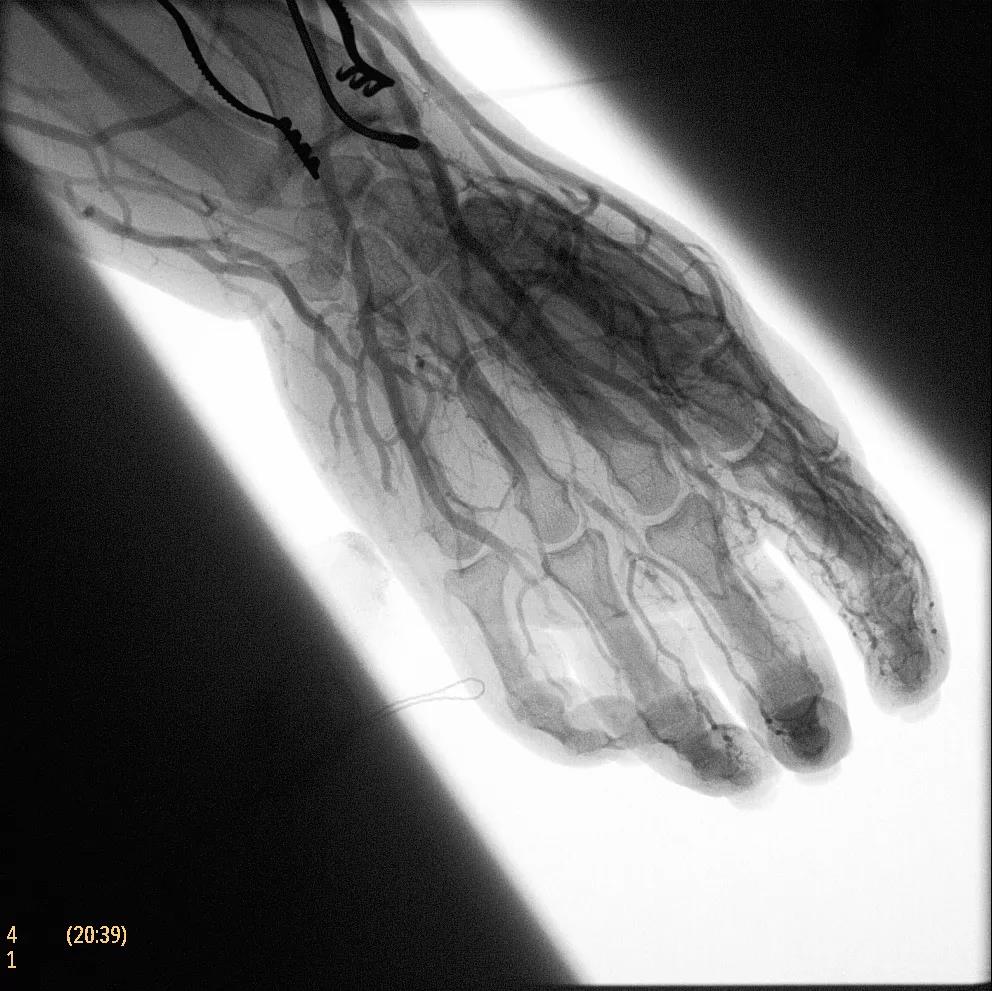

據(jù)器械之家了解到,移動(dòng)式C型臂是X射線(xiàn)系統(tǒng),可帶入手術(shù)室(OR),在整形外科、創(chuàng)傷和血管手術(shù)等各種手術(shù)過(guò)程中提供實(shí)時(shí)圖像引導(dǎo)。Zenition70使醫(yī)院能夠最大限度地提高OR性能,增強(qiáng)臨床能力并為員工提供高質(zhì)量的用戶(hù)體驗(yàn)。

為了獲得清晰的高質(zhì)量圖像,Zenition 70 采用了與公司Azurion平臺(tái)相同的圖像處理算法,可提供患者解剖結(jié)構(gòu)的高清可視化和更大的可視區(qū)域。飛利浦的MetalSmart軟件等功能可確保圖像質(zhì)量,該軟件可自動(dòng)調(diào)整圖像的對(duì)比度和亮度,以便在視野中存在金屬物體(如植入物)時(shí)提高圖像質(zhì)量 - 這一特性使Zenition 70在整形外科中特別有用。